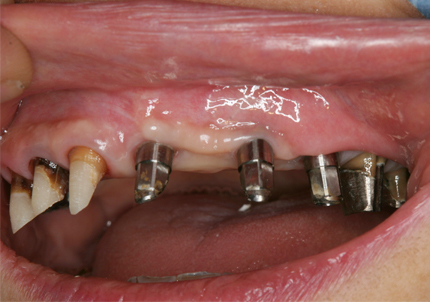

14.インプラント埋入(2016年8月24日)

15.右下6番近心根抜歯(2016年12月12日)

↑術後1か月(2017年1月7日)

16.下顎インプラント補綴治療終了(2017年4月8日)